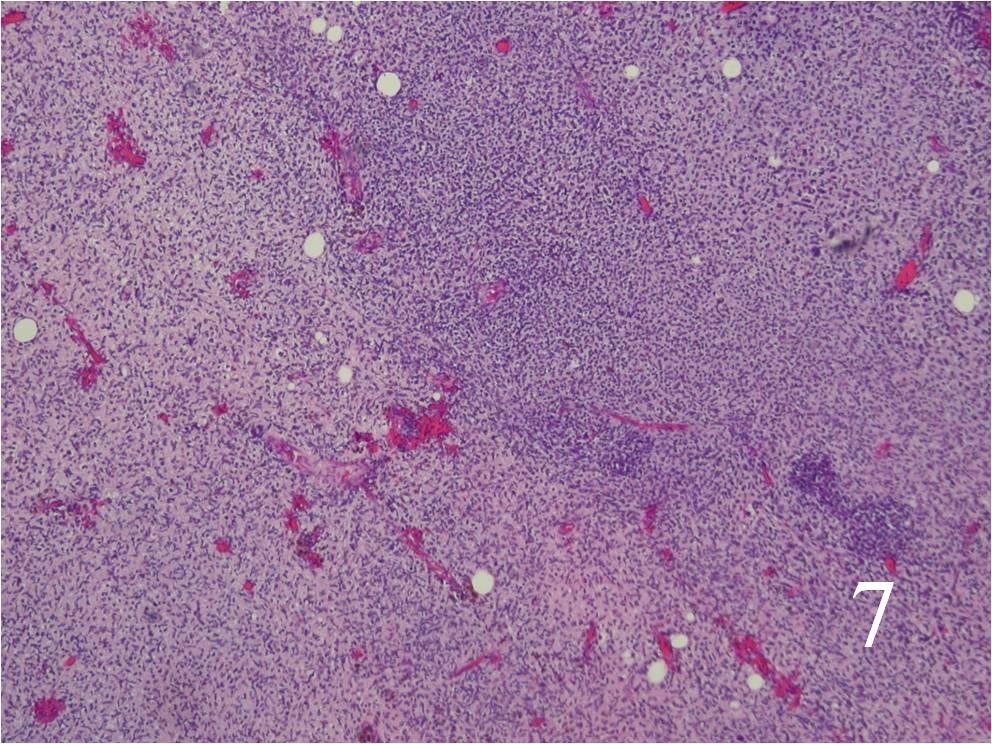

Microscopic

- Resembles fibrosarcomas

- Usually high grade features

- Spindle cells with markedly irregular contours (Fig. 7, 8)

- Nuclei are comma-shaped

- Cells are arranged in sweeping fascicles

- Extensive perineural and intraneural spread

- Proliferation of tumor into subendothelial zone of the vessels

Fig. 7 Low power and high power (Fig. 8) magnification on H&E staining shows a spindle cell neoplasm with high cellularity, abnormal mitotic features and nuclear atypia. The cells are arranged in a somewhat fascicular manner.